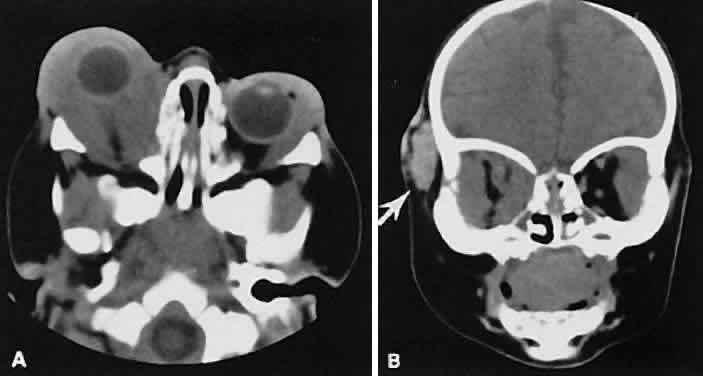

An appreciation for the various pathologic processes that affect the orbit is facilitated by an understanding of the normal orbital anatomy (Fig. 1). The orbit is a pyramid-shaped bony structure bounded inferiorly by the maxillary sinus, medially by the ethmoidal sinus, and superiorly by the frontal sinus. The sphenoidal sinus is situated posteriorly along the medial orbital wall and has a common wall with the optic canal. The lacrimal gland lies within its fossa located in the superior temporal aspect of the orbit and can be seen on both axial and coronal views.

The extraocular muscles (EOMs), with the exception of the inferior oblique, originate from the anulus of Zinn in the orbital apex. The inferior oblique takes its origin from the frontal process of the maxilla and is seen occasionally on CT imaging. The superior oblique, after originating from the anulus, courses along the superior nasal orbital wall just above the medial rectus muscle before passing through the trochlea. The rectus muscles conveniently form a muscle cone, which is sometimes helpful in terms of differential diagnosis. Before thinner axial slices and multiplanar imaging were available, an enlarged inferior rectus muscle often was imaged as an apical mass, especially if dysthy-roid optic neuropathy was present. The importance of imaging from two different planes cannot be overemphasized in this situation.

The superior ophthalmic vein (SOV) is an important vascular structure to recognize. It begins in the superior nasal quadrant near the trochlea before coursing posteriorly and laterally beneath the superior rectus muscle, exiting the orbit through the superior orbital fissure. Drainage is into the cavernous sinus. Asymmetric enlargement, especially in the presence of an ipsilateral cavernous sinus enlargement, suggests a vascular anomaly, which may require selective carotid angiography for further definition. Enlargement of one or multiple EOMs in this setting is likely. The SOV also may be enlarged as a result of any process impeding drainage from the orbital apex, such as dysthyroid orbitopathy or metastatic disease.

The optic nerve occupies the central intraconal space. By necessity, the nerve has a certain amount of slack, which is necessary to permit movement of the globe. In the axial plane, the optic nerve has an undulating course and thus may appear thicker or thinner as a result of partial volume averaging as it passes in and out of the axial plane. It is imperative to recognize this normal pattern for proper interpretation of axial images.

The optic nerve itself is invested by the same meningeal layers that cover the brain, and the intracranial space may extend along the course of the optic nerve to the back of the globe. Enlargement of this space may be recognized as pseudomeningoceles of the optic nerve sheath. It is sometimes possible to tell whether the nerve, the sheath, or both are enlarged by CT scanning, although MRI affords the better view.